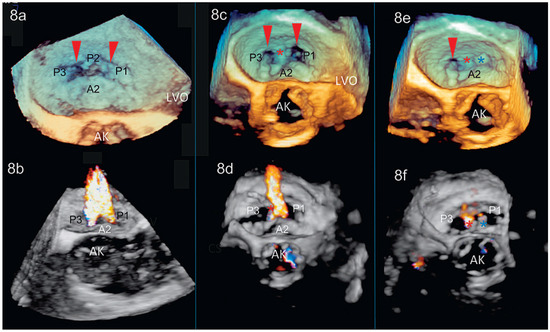

Dreidimensionale Echokardiographie zur Beurteilung der Mitralklappe

by Patric Biaggi, Christian Felix, Matthias Greutmann, David Hürlimann, Dominique Bettex and Felix C. Tanner

Using two-dimensional echocardiography, the complex anatomy of the mitral valve needs mental reconstruction into its three-dimensional shape. The power of both transthoracic and transesophageal three-dimensional echocardiography (3DE) lies in its possibility of showing the complex mitral valve anatomy in one single image, as [...] Read more.

Using two-dimensional echocardiography, the complex anatomy of the mitral valve needs mental reconstruction into its three-dimensional shape. The power of both transthoracic and transesophageal three-dimensional echocardiography (3DE) lies in its possibility of showing the complex mitral valve anatomy in one single image, as opposed to the mental reconstruction based on multiple two-dimensional images and schematic assumptions. Several 3DE modalities are used in daily life, including real time (“live”) modes as wells as postprocessed images. 3DE is of special interest in the evaluation of mitral stenosis, complex mitral valve prolapse and mitral valve prostheses. It has an established role in the perioperative mitral valve assessment during mitral valve surgery as well as during percutaneous mitral valve procedures. Limitations of 3DE are relatively low frame rates, an important learning curve as well as timeconsuming processing. Full article